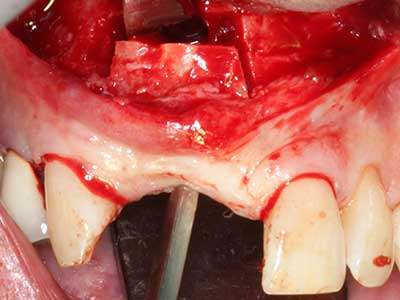

El tejido óseo no solo tiene un contenido puramente mineral, sino que también presenta una importante proporción de fibras de colágeno. Esto no solo garantiza una buena resistencia a la presión, sino también una cierta flexibilidad, que puede aprovecharse para la realización de aumentos. En la plastia de expansión clásica a efectos de una partición ósea, la cresta maxilar atrofiada se divide en su eje longitudinal y, tras alcanzar una profundidad de osteotomía suficiente, se extiende con cuidado (fig. 13-16), en un caso ideal sin desperiostizar de forma visible el maxilar (Brugnami, Caiazzo et al. 2014, Stricker, Fleiner et al. 2014). Los sistemas de tornillos y placas con distancia de expansión creciente han demostrado su eficacia para distanciar entre sí las dos tablas óseas por debajo del umbral de rotura. Por regla general, se requieren anchuras de hueso residual de al menos 3 a 4 mm (Chiapasco, Zaniboni et al. 2006) para garantizar una flexibilidad y una cobertura ósea suficientes de los implantes que van a incorporarse. En caso necesario, una osteotomía de descarga vertical unilateral o bilateral puede mejorar la flexibilidad. Como alternativa a la técnica clásica se ha descrito una combinación con otras técnicas de aumento, sobre todo en la parte bucal.

Con el uso de sierras piezoeléctricas la división se efectúa de forma especialmente cuidadosa y sin pérdidas importantes de las dimensiones, por lo que no se han encontrado diferencias significativas entre los implantes realizados en el maxilar dividido y en la cresta alveolar no deficitaria (Chiapasco, Zaniboni et al. 2006, Danza, Guidi et al. 2009). No obstante, precisamente en la partición profunda y limitada de forma local, es preciso asegurarse de que exista una adecuada irrigación por agua para evitar que se produzcan sobrecargas térmicas en las áreas de osteotomía apical.